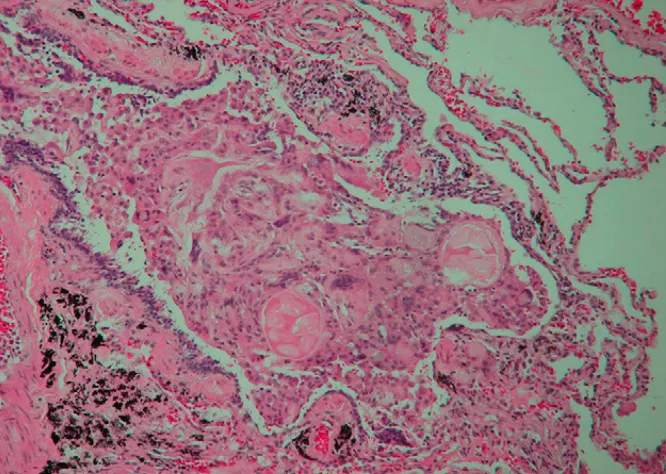

胸腔镜下肺活检病理如下:

DAB的组织学表现与慢性吸入一致,包括伴有异物的多灶性细支气管中心性炎症,以及细支气管管腔内可见的包涵有异物的巨大细胞。在DAB的肺泡导管和肺泡内也可以发现异物,有些细支气管可能是被密密麻麻的疤痕组织覆盖。在这个案例中,肺活检病理证实细支气管内存在食物样颗粒和炎症图像与误吸相符合。